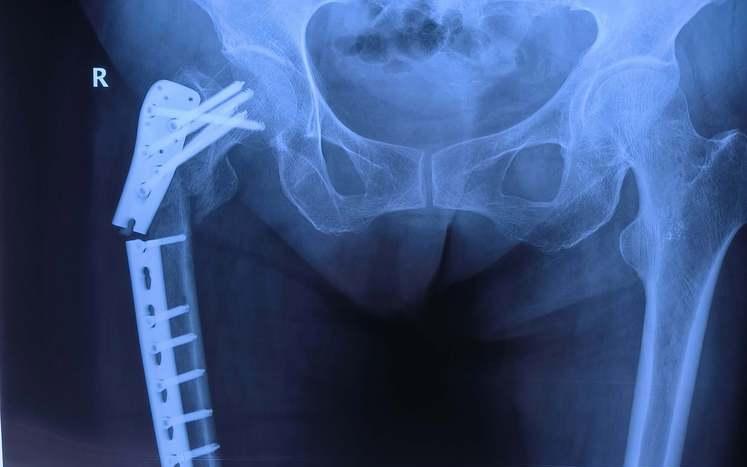

患者宋某,女,48岁,在2023年7月因跌倒致髌骨骨折,在骨科行髌骨骨折内固定术后出院,2024年10月返回我院取出髌骨内固定。在骨折治疗中,内固定是一种常见且重要的手术方法,它通过金属装置将骨折断端固定在一起,以促进骨折的愈合和恢复。然而,随着骨折的愈合和康复,患者常常会面临一个问题:内固定装置是否需要取出?下面,我们就让骨科医生告诉您。